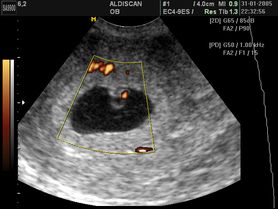

Rozwój płodu

Pierwszy trymestr ciąży - badanie USG, ciąża tydzień po tygodniu

Rozwój płodu - okresy życia prenatalnego, rozwój płodu w poszczególnych miesiącach